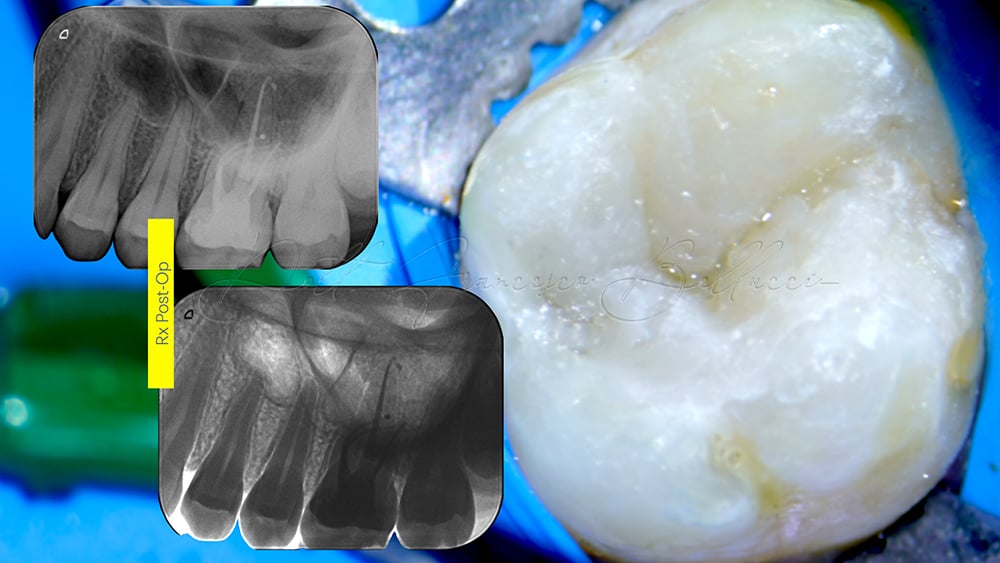

La fase di otturazione è stata eseguita mediante utilizzo del cemento calcio silicato Total-Fill, con i coni di guttaperca dedicati.

Dopo l’otturazione canalare veniva eseguita una ricostruzione diretta della cavità di accesso (Fig. 3) in attesa di eseguire a distanza di tempo un restauro di tipo indiretto.

Si evidenzia dopo 3 mesi la completa assenza di sintomatologia e una assenza di lesioni periapicali (Fig. 4).